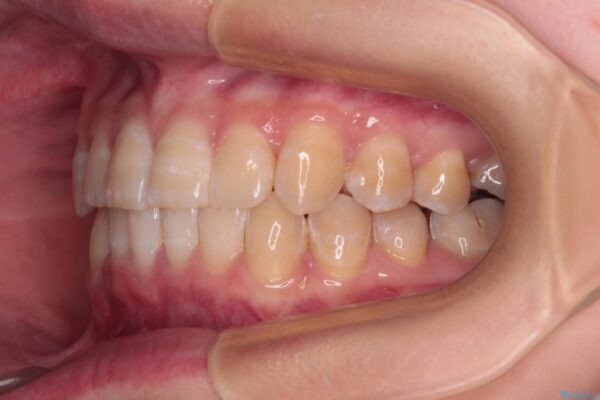

下顎の八重歯を気にして来院された患者様です。

下顎前歯にデコボコが集中していたため、顎間ゴムによる後方移動とIPR(歯と歯の間を削ること)により歯列を整えることとしました。

治療前、下顎前歯のデコボコが集中しており、奥歯の咬み合わせは、上顎に対して下顎が前方位にある状態でした。下顎の歯列を後方へ移動させる治療はインビザラインの得意とするところですので、1年程度で無事に治療を終えることができました。

治療途中

• 【モニター】下顎前歯のデコボコをインビザラインできれいに 治療途中画像